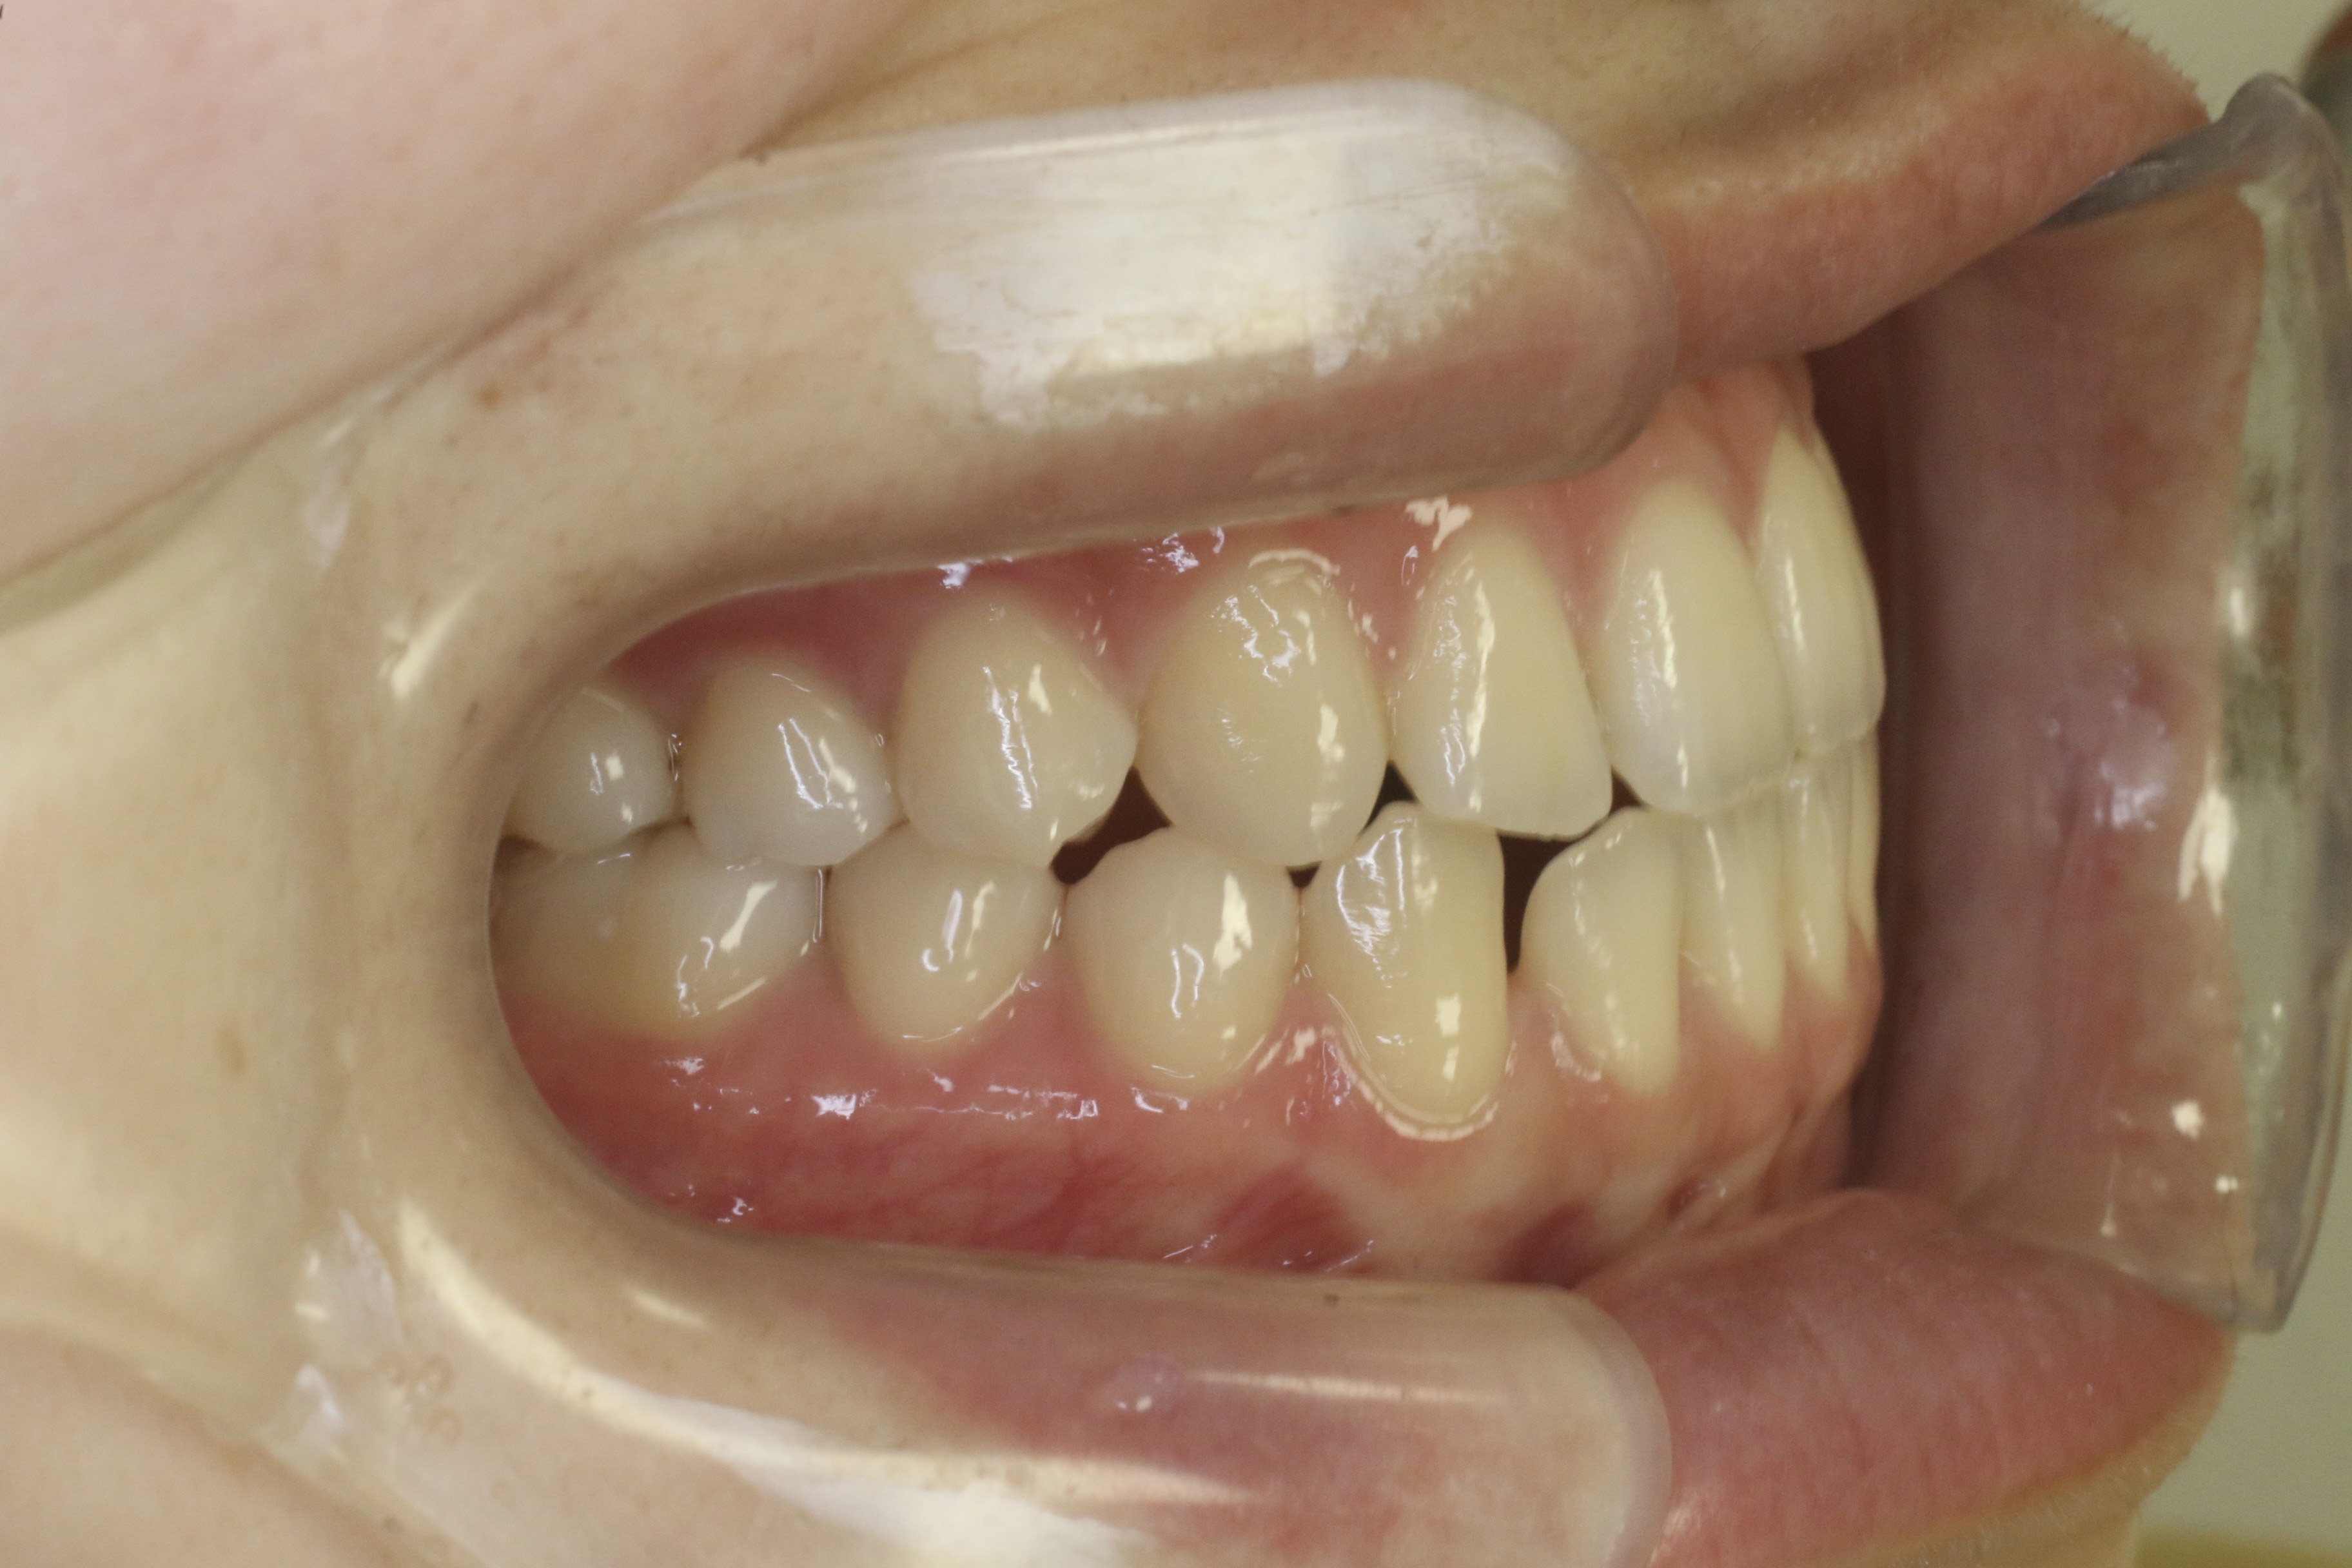

歯のデコボコを治したい

年齢層 20代

性別 女性

主訴 【主訴】歯のデコボコを治したい 【診断・症状】上下凸凹

治療費用 検査・診断:38,500-/裏側矯正治療:1,397,000-(※全て税込)

治療期間 約3年半(45回)

抜歯 有(上4,4、下 4,4)

矯正の装置 裏側矯正(舌側矯正)

副作用、リスク 歯肉退縮,歯根吸収,疼痛,咬合の違和感,装置の違和感,虫歯,歯肉炎